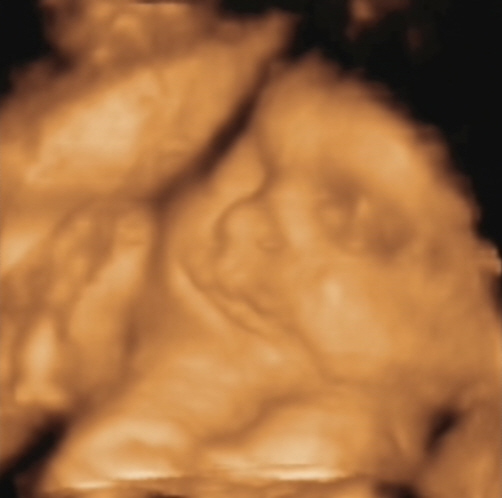

álmaim bébjárgánya